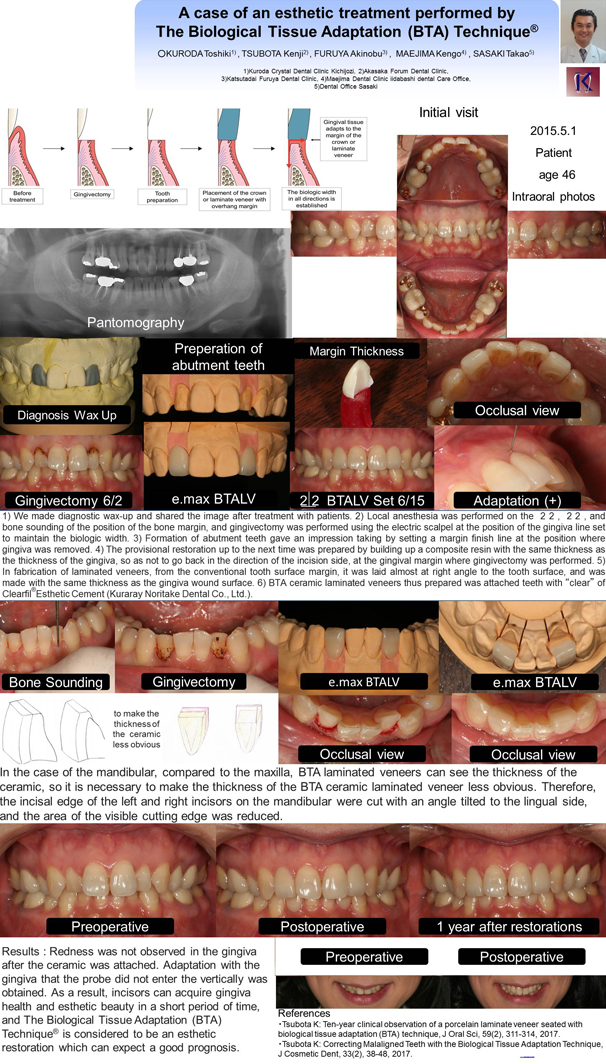

テーマは「(BTA)TechniqueRを用いて審美的歯科治療した1症例」

前歯の暗い感じを気にして、4ヵ月後の海外への転勤までに見た目を綺麗にしたいと来院された前歯の位置関係を、(BTA)TechniqueRを用いて、殆ど削らずに、来院回数2回で、審美的なセラミックを装着し、歯肉の健康と審美性を得ることができた。The Biological Tissue Adaptation (BTA) TechniqueRは良好な予後が期待できる審美的修復と考えられる。この1症例を大判のポスターを用いて学会発表致しました。

テーマ ; A case of an esthetic treatment performed by The Biological Tissue Adaptation (BTA) TechniqueR

発表演者 ; Kuroda Toshiki

Patients : The patient was a woman who cared about the dark feeling of the incisors. It was the main complaint that she wanted to make beautiful appearance before the transfer to overseas after 4 months. The case is due to lingual dislocation of incisors

Treatment Planning and method : Surgical operations such as crown lengthning or orthodontic treatment become necessary in order to prepare incongruity of lingual dislocation and gingival margin. This time, because the time period is limited, they can not be applied. Therefore, esthetic treatment performed by the Biological Tissue Adaptation (BTA) TechniqueR was applied.

Results of Treatment and Conclusion : Redness was not observed in the gingiva after the ceramic was attached. Adaptation with the gingiva that the probe did not enter the vertically was obtained. As a result, incisors can acquire gingiva health and esthetic beauty in a short period of time, and The Biological Tissue Adaptation (BTA) TechniqueR is considered to be an esthetic restoration which can expect a good prognosis. We will continue to observe this case.